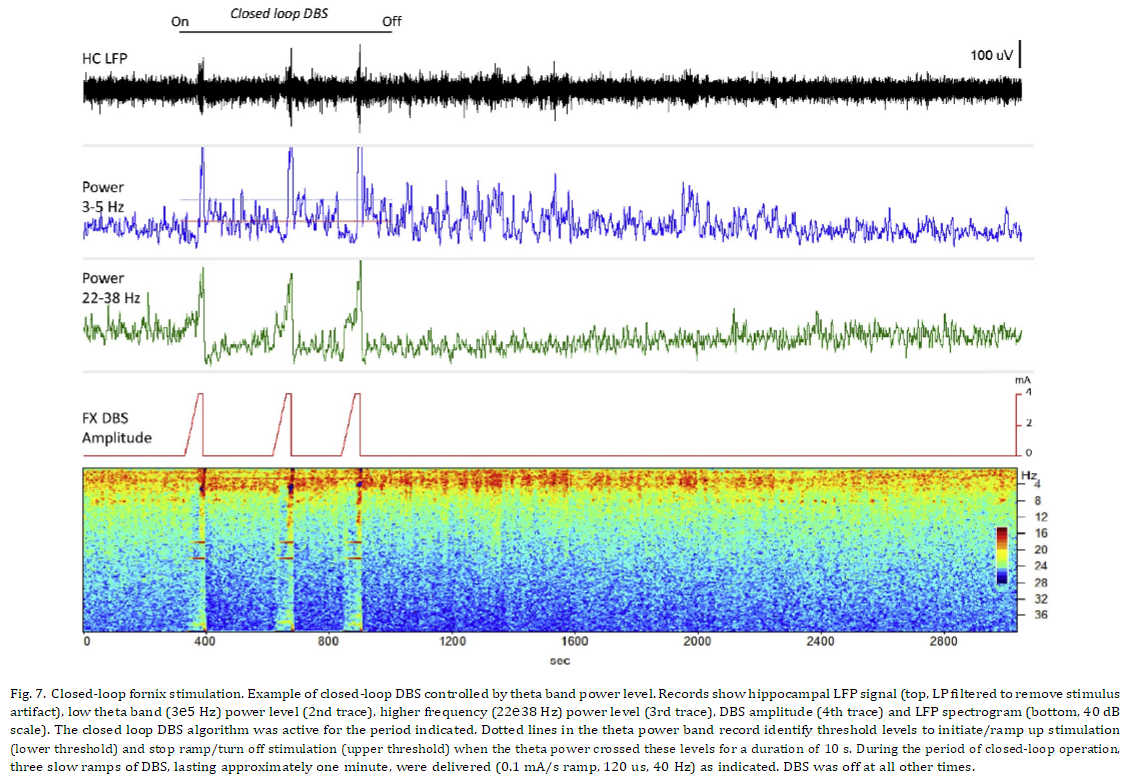

해마 활동의 폐쇄 루프 변조

Fornix DBS는 비만 치료를 받고 있는 피험자에서 자극 유발 기억의 초기 관찰을 기반으로 알츠하이머병 치료제로 조사 중입니다 [31]. 이 초기 관찰에 이어 경미한 알츠하이머 환자의 fornix DBS에 대한 6명의 피험자 파일럿 연구가 이어졌습니다 [7]. 6명 중 2명의 피험자에서 자극이 5e6V의 "상대적으로 높은" 수준으로 전달되었을 때 자서전적 기억과 관련된 유사한 역치 의존 현상이 보고되었습니다. 우리 동물에서 관찰된 후속 네트워크 상태 변화는 이러한 임상 경험의 전기생리학적 상관관계를 나타낼 수 있습니다. 이 연구에 사용된 장치는 인간 대상에서 신경망 활동과 DBS에 의해 유도된 변화를 만성적으로 기록할 수 있는 기회를 제공합니다. 증상 상태, 임상적 개선 또는 다양한 장애의 특정 행동 사건과 관련된 네트워크 활동을 관찰할 수 있는 능력을 갖추면 궁극적으로 DBS 요법으로 결과를 개선해야 합니다. 서로 다른 네트워크 장애에서 원하는 상태에 대한 근본적인 이해는 결국 적응형 DBS 알고리즘의 개발을 지원하여 신경 활동을 특정 범위로 보다 정확하게 조절합니다. 우리는 이전에 Papez 네트워크의 활동을 억제하고 해마의 흥분성을 정의된 수준으로 감소시키는 것이 가능하다는 것을 입증했습니다. 직접 해마 또는 전방 시상 DBS를 사용하여 둘 다 간질 치료를 위해 조사 중입니다. 이러한 효과는 운동 장애에 일반적으로 사용되는 연속 고주파 자극과 비교하여 저주파(40~50Hz) 폐쇄 루프 자극으로 얻을 수 있으며 일반적으로 새로운 DBS 적응증의 거의 모든 조사에 채택됩니다. 그림 7에 표시된 예는 유사한 자극 매개변수와 폐쇄 루프 fornix DBS를 사용하여 이 네트워크에서 활동을 구동하는 것도 가능함을 보여줍니다. 낮은 자극 수준에서 억제가 발생하는 이 흥분 효과의 신중한 진폭 의존성은 특히 급성 임상 반응이 쉽게 나타나지 않는 상황에서 매개변수 적정 중에 신경 활동에 대한 DBS 효과를 직접 관찰할 수 있는 가치를 분명히 강화합니다. 현재 작업은 이러한 관찰에 분명한 한계가 있습니다. 상대적으로 적은 수의 피험자 집단에서 나온 것입니다. 그러나 보고된 결과는 깨어 있는 대형동물에서 수년간의 만성 기록에 걸쳐 도출되었으며 DBS에 대한 반응으로 신뢰할 수 있고 반복적인 측정을 나타냅니다. 또한 본질적으로 동일한 실험적 접근 방식을 사용하는 이전 연구의 결과는 Papez 회로의 특정 대상에서 DBS에 의해 생성된 해마 활동에 대한 다양한 효과를 강조하는 비교자를 제공합니다. 이 모든 작업은 일반 동물에서 수행되었으며 만성 질환 모델, 따라서 임상 분야에 대한 외삽법은 빈약합니다. 그러나 정상 상태에서 서로 다른 네트워크가 DBS에 어떻게 반응하는지 정의하는 것은 병태생리학적 조건에서 DBS 요법의 작용 메커니즘을 더 잘 이해하는 데 근본적인 것으로 보이며 표적 및 자극 매개변수 선택에 대한 통찰력을 제공할 수 있습니다. 결론적으로 설명된 결과는 Papez 회로에만 해당되지만 이 대형 동물 모델은 DBS 효과를 탐색하기 위한 프로토타입 네트워크 및 차세대 기술을 위한 테스트 베드 역할을 할 수 있습니다. 이러한 관점에서 이러한 연구는 LFP를 폐쇄 루프 제어 신호로 사용하여 완벽하게 이식 가능한 DBS 시스템을 통해 실시간으로 네트워크 활동을 궁극적으로 모니터링하고 원하는 엔드포인트로 변조할 수 있는 잠재력을 입증했습니다. 기저핵 LFP 바이오마커를 기반으로 인간 피험자에서 파킨슨병에 대한 폐쇄 루프 DBS의 초기 시연이 여러 그룹에서 보고되었습니다 [32 e34]. 지금까지 이러한 연구는 DBS 리드에 대한 경피적 접근을 필요로 하는 외부 기반 제어 시스템을 사용하여 상대적으로 짧은 기간 동안 병원 내에서 엄격하게 수행되었습니다. 여기에 사용된 이식형 시스템의 인간 사용에 대한 초기 보고서는 최근에 나타났으며 다양한 장애의 여러 DBS 표적에서 만성 LFP 기록을 설명합니다 [35 e39]. 이 시스템을 사용하는 인간 대상에서 폐쇄 루프 DBS의 초기 파일럿 조사가 현재 진행 중입니다.